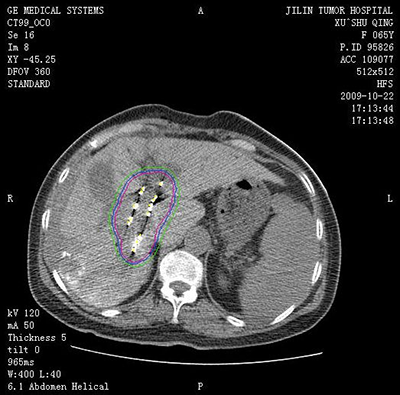

![]() | ![]() |

| (肺癌的介入治疗) | (盆腔恶性肿瘤的介入治疗) |